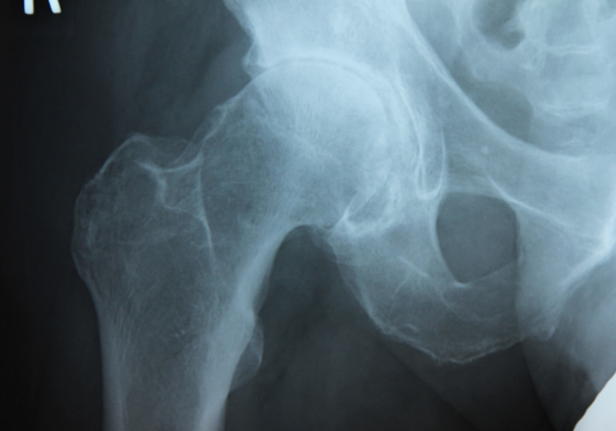

変形性股関節症の診断

レントゲンで狭くなった股関節の隙間や骨の棘を確認することで診断します。

変形性股関節症の治療

まずは炎症を抑える薬や湿布、塗り薬を使用し、消炎を図ります。並行して生活指導を行います。抵抗はあるかもしれませんが、杖を使うと痛みが楽になることがあります。また肥満がある方はダイエットを考えてもらい、また週2-3回程度のプールでの運動は痛みを悪化させず、減量を促すことに有効です。これらの保存療法でも症状が取れない場合は手術療法を考え、近隣の病院へ紹介することもあります。